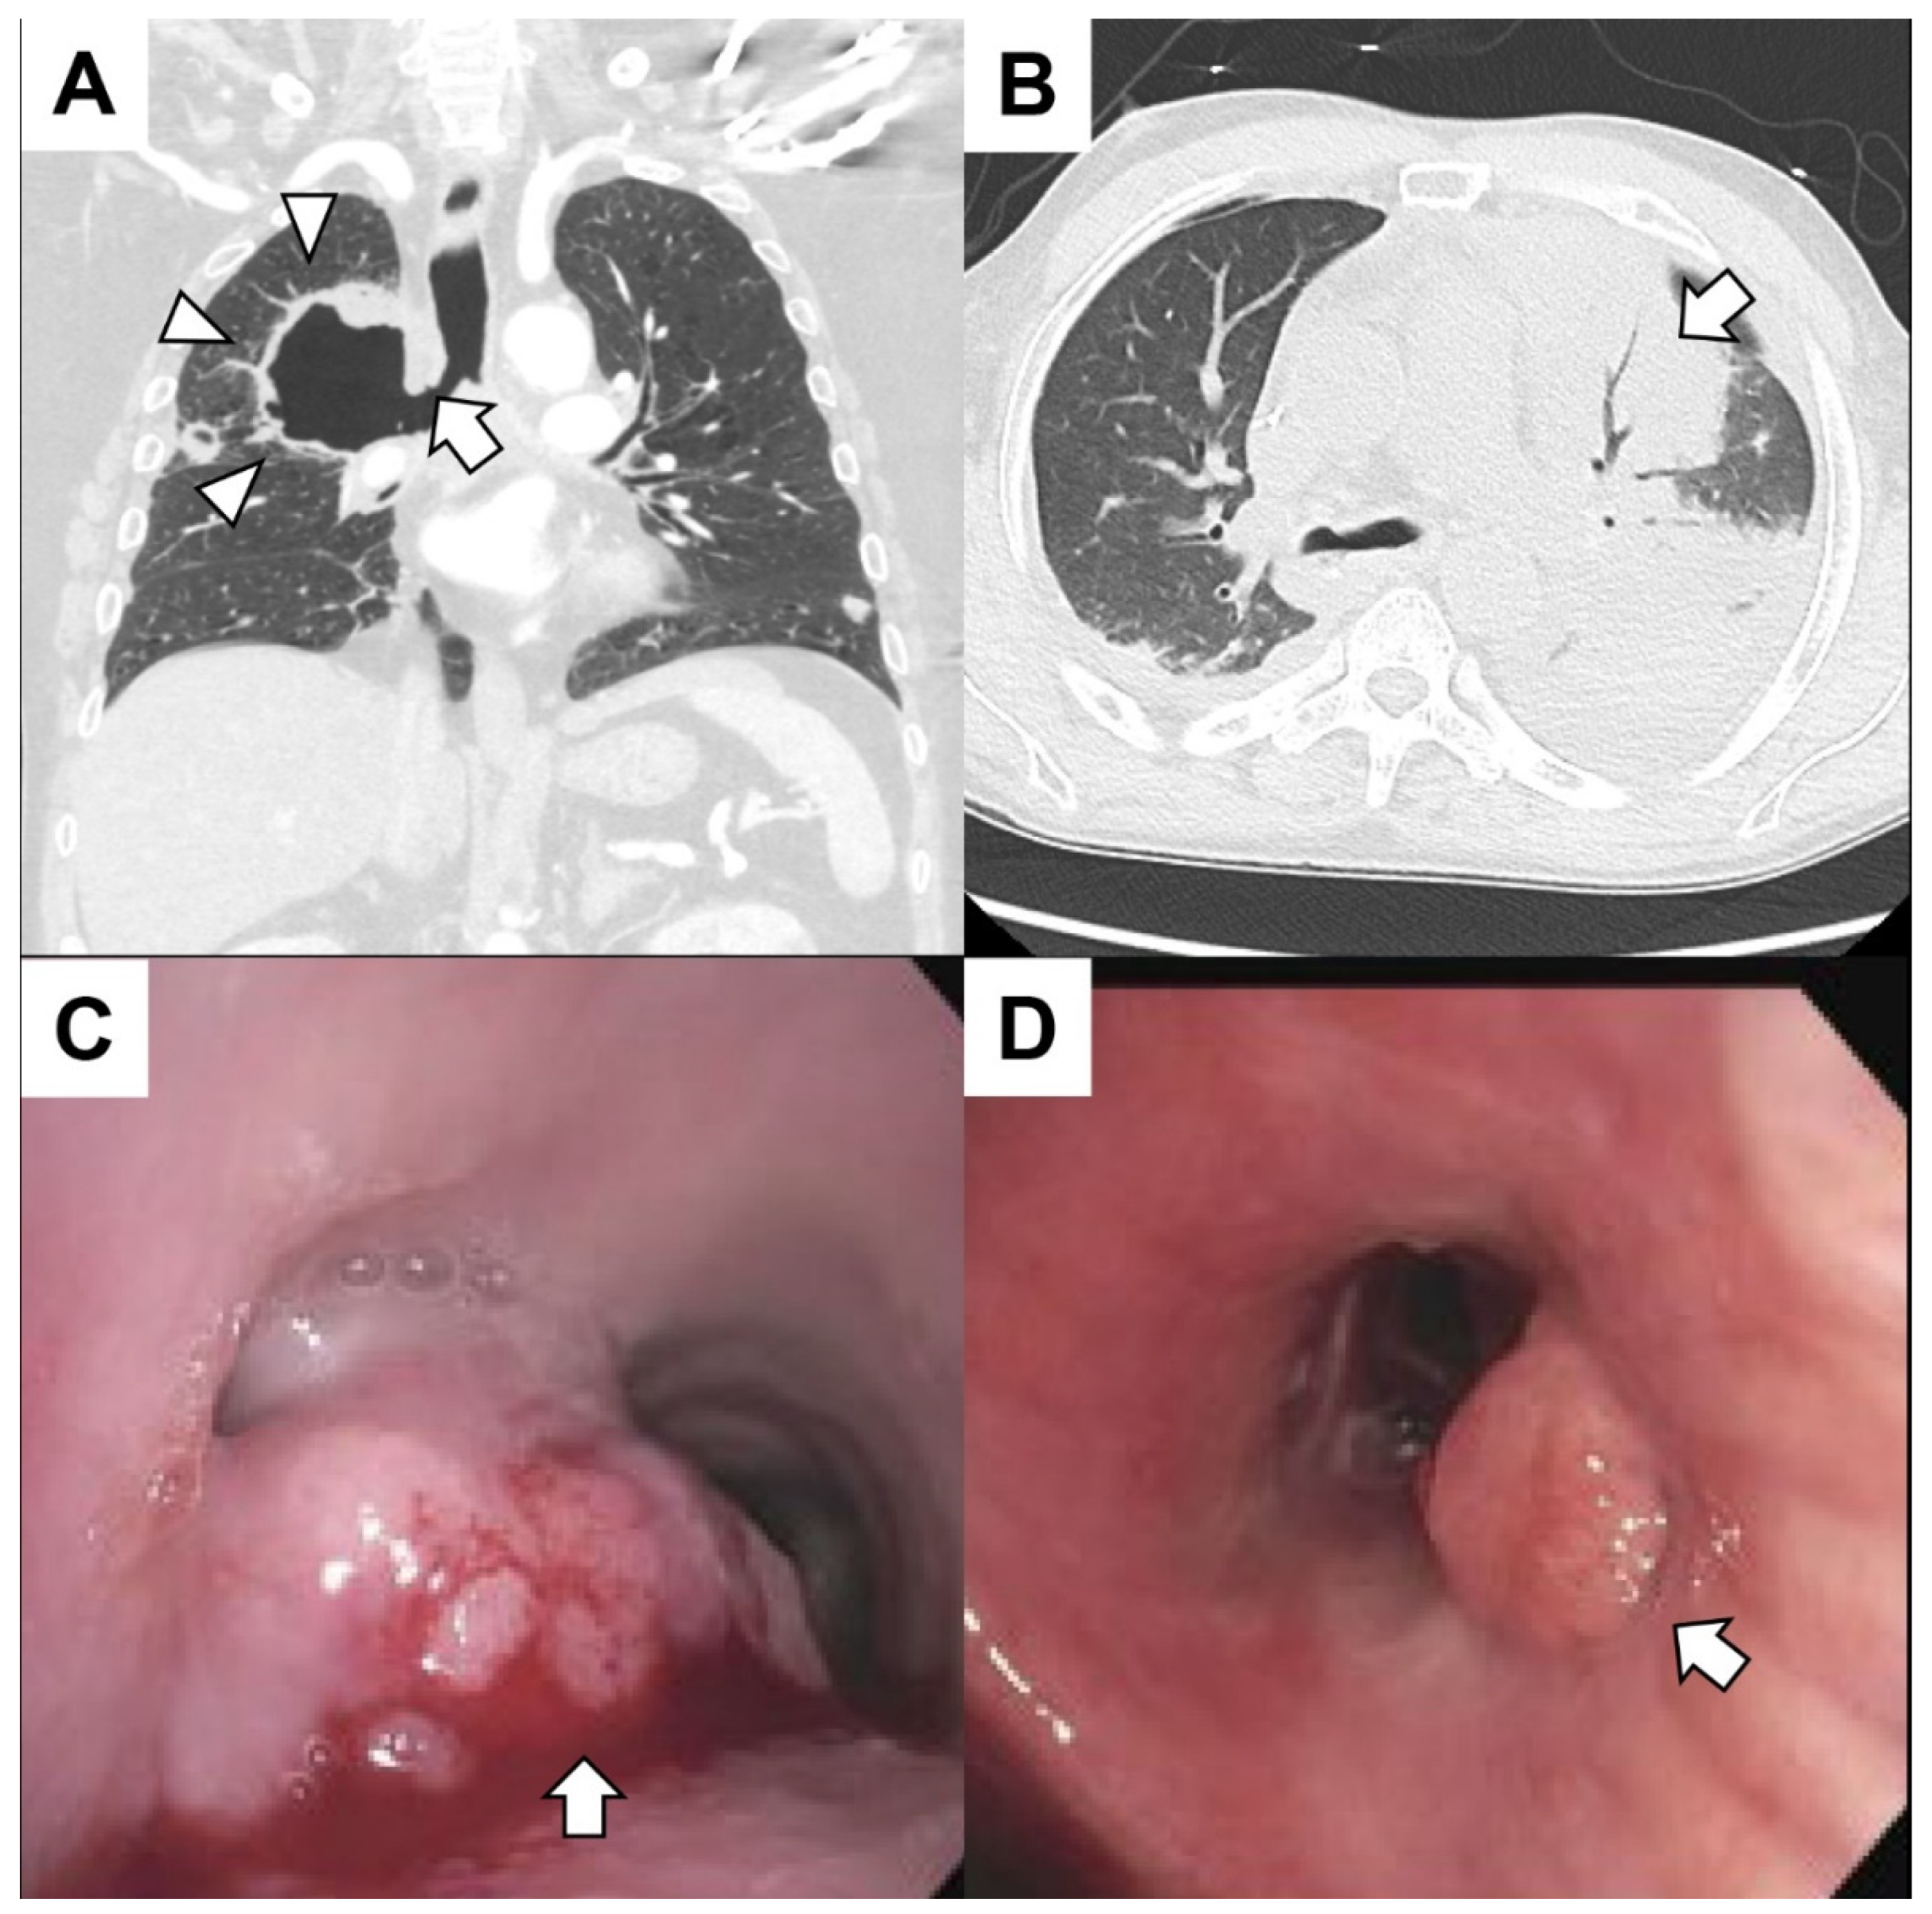

5.1. Primary Lung Cancer

5.2. Pulmonary Metastasis